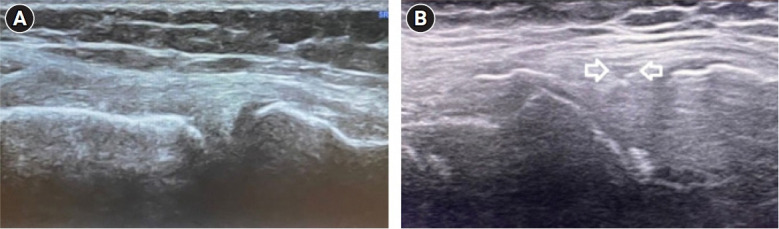

Abstract Image